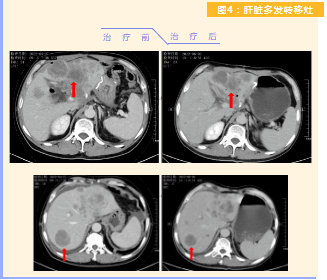

患者完成1周期治療后,上腹部疼痛癥狀基本消失,梗阻性黃疸癥狀緩解,腫瘤指標(biāo)下降(圖1),肺部多發(fā)轉(zhuǎn)移灶消失和縮?。▓D2),雙肺門淋巴結(jié)縮小(圖3),肝臟多發(fā)轉(zhuǎn)移灶縮?。▓D4)。